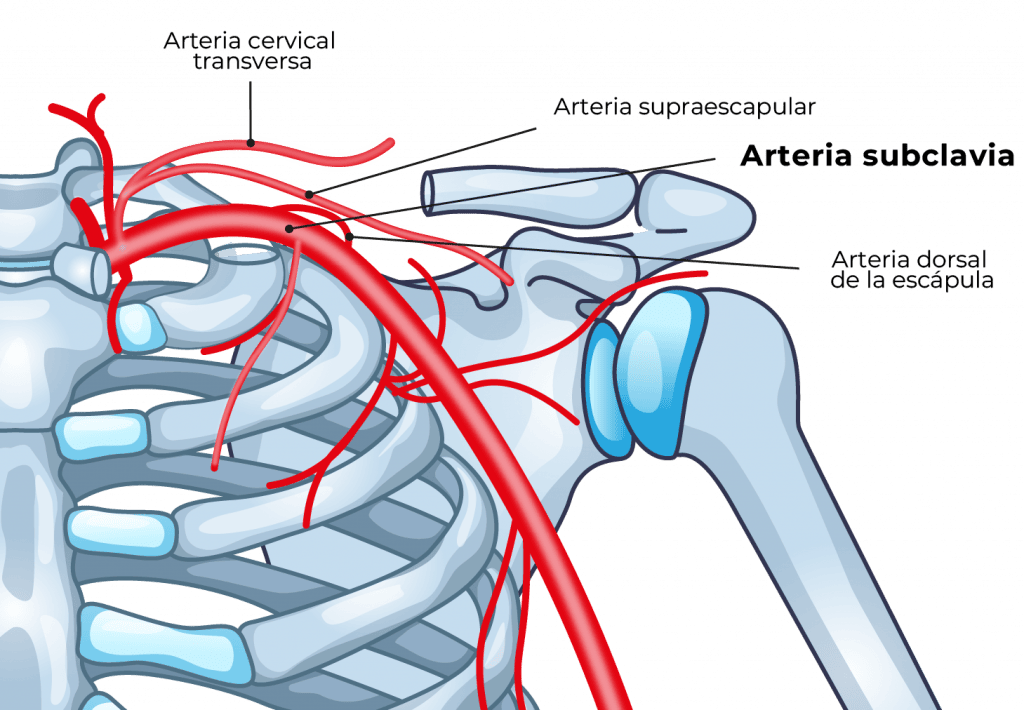

Arteria subclavia

La arteria subclavia asciende desde el mediastino superior por la cúpula pleural y luego cursa sobre la cara superior de la primera costilla, entre las inserciones de los músculos escalenos anterior y medio, por debajo del punto medio de la clavícula.

La inserción del músculo escaleno anterior separa la arteria de la vena subclavia y es de los pocos sitios anatómicos en los cuales una arteria y su vena acompañante se encuentran separadas.